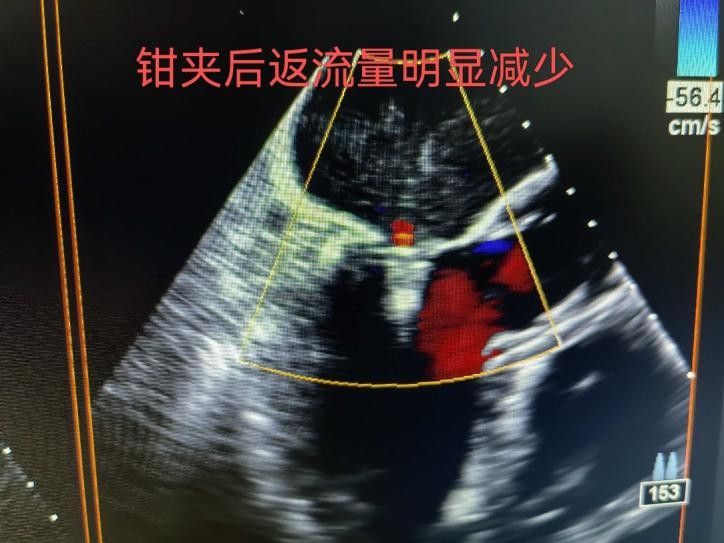

手术于11月4日下午进行,通过股静脉穿刺送入夹合器,在食道超声实时引导下,精准植入2枚瓣膜夹修复二尖瓣。整个过程历时约2小时,术中出血量仅50ml。术后次日,患者即可下床活动,复查显示EF提升至46%,二尖瓣返流面积缩小至3.0cm²,左心房缩小至66mm,胸闷、气短症状明显缓解。

2.精准定位:在食道超声和X线引导下,将夹合器送达二尖瓣位置,通过夹合病变瓣膜减少返流;